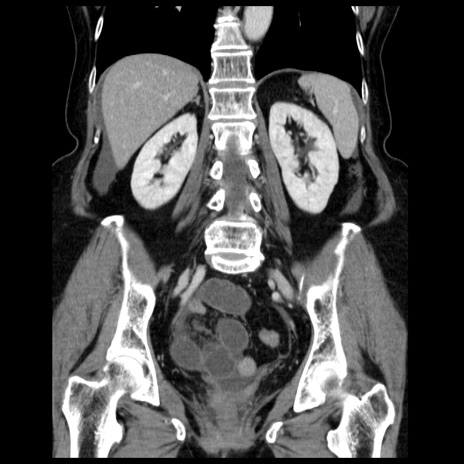

症例13(冠状断像)

【症例】70歳代女性

【主訴】腹痛、嘔吐

【現病歴】15時間程前(昨晩)より腹痛あり。今朝になっても症状の改善なく、嘔吐あり。腹痛も増悪あり、救急外来受診。

【既往歴】子宮癌全摘術後

【身体所見】意識清明、BP 121/72mmHg、P 74bpm、SpO2 100%(RA)、腹部:平坦・軟、腸雑音ほぼ聴取せず。下腹部・心窩部・臍左上に圧痛あり。反跳痛なし。

【データ】WBC 10600、CRP 0.15